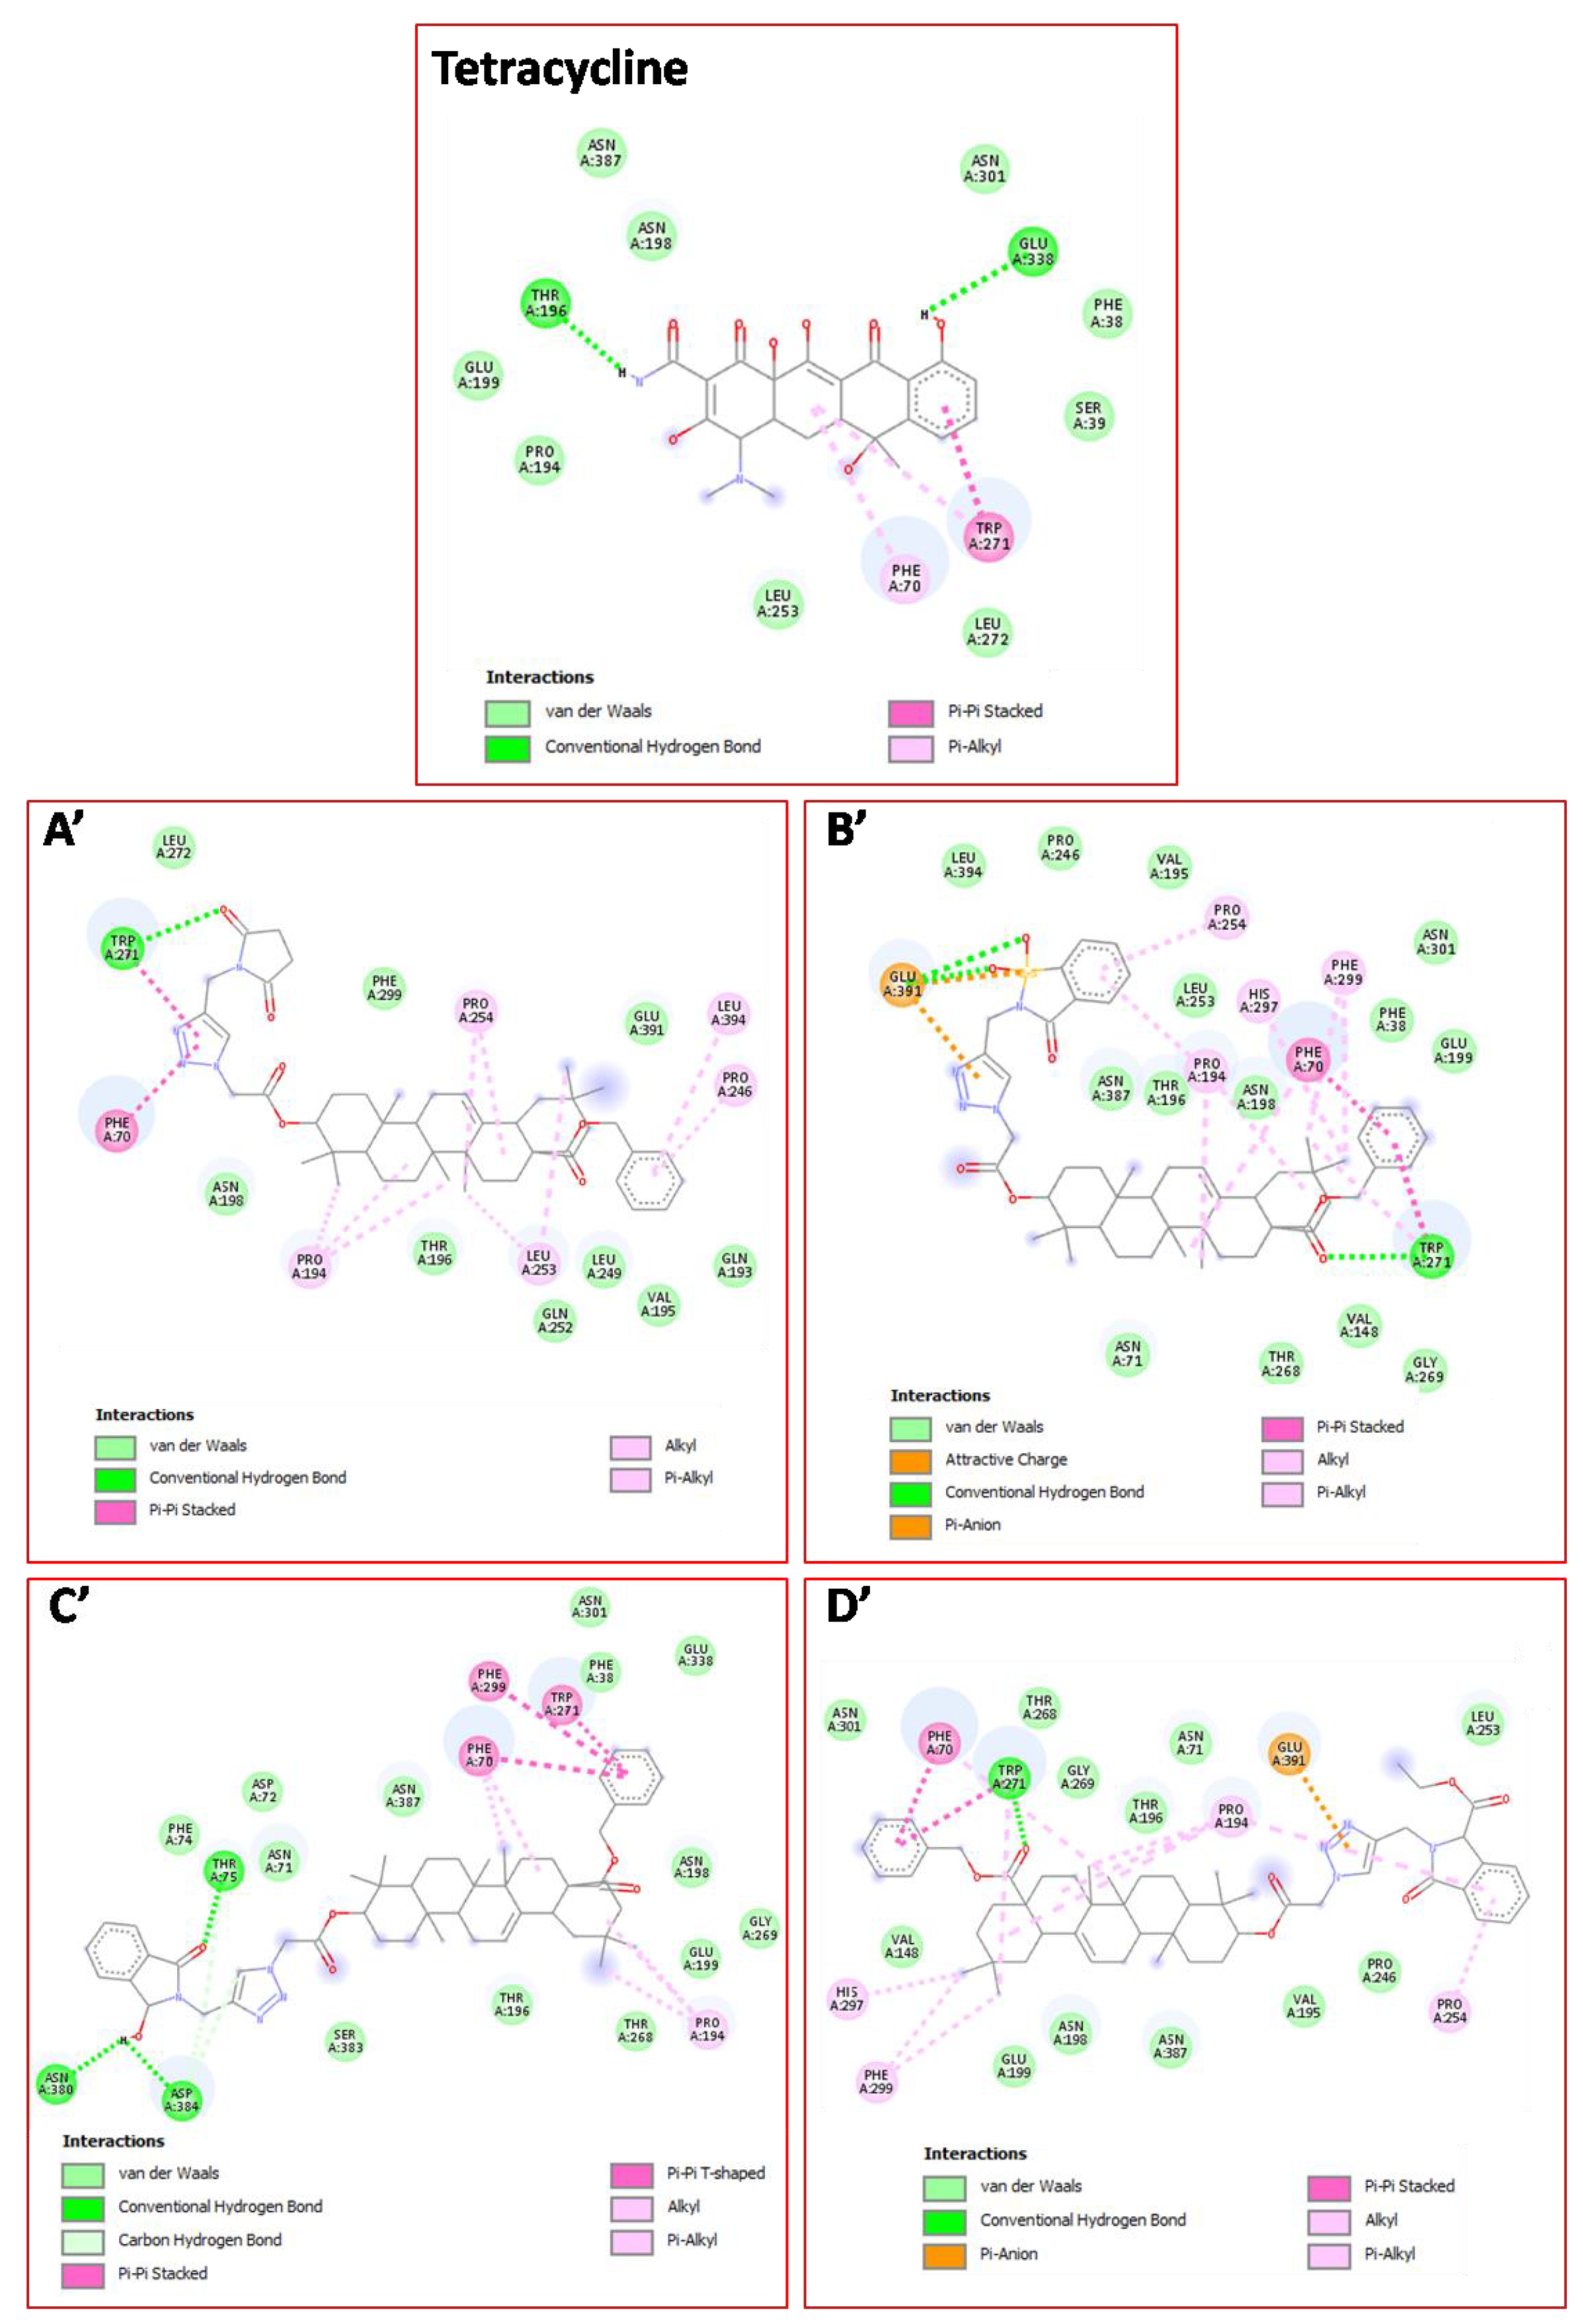

| 18c | van der Waals: Gln193, Val195, Thr196, Asn198, Leu249, Gln252, Leu272, Phe299, Glu391; H bond: Trp271*(3.13); Alkyl/Pi–Alkyl:Pro194(3.92)(4.90)(5.06), Pro246(5.14), Leu253(4.11)(5.26), Pro254(4.85)(5.21), Leu394(5.37); Pi-Pi: Phe70(4.10), Trp271(4.33). | −11.7 |

| 18d | van der Waals: Phe38, Asn71, Val148, Val195, Thr196, Asn198, Glu199, Pro246, Leu253, Thr268, Gly269, Asn301, Asn387, Leu394; H bond: Trp271*(3.15), Glu391**(3.27)(3.38); Alkyl/Pi–Alkyl: Phe70(5.14), Pro194(4.86), Pro254(4.77), Trp271(4.89), His297(4.07), Phe299(4.43) (4.76); Pi-Pi: Phe70(3.87), Trp271(4.66); Pi-Anion: Glu391(3.81). | −12.0 |

| 18h | van der Waals: Phe38, Asn71, Asp72, Phe74, Thr196, Asn198, Glu199, Thr268, Gly269, Asn301, Glu338, Ser383, Asn387; H-bond: Thr75*(3.13), Asn*380(2.55), Asp384*(2.12); C-H bond: Thr75(3.28), Asp384(3.71)(3.76); Alkyl/Pi–Alkyl: Phe70(5.05)(5.26), Pro194(4.27)(5.19); Pi-Pi: Phe70(5.06), Trp271(4.47),Phe299(5.16). | −12.3 |

| 18k | van der Waals: Phe38, Asn71, Val148, Val195, Thr196, Asn198, Glu199, Pro246, Leu249, Gln252, Leu253, Thr268, Gly269, Asn301, Asn387; H-bond: Trp271*(3.25); Alkyl/Pi–Alkyl: Phe70(5.28), Trp271(4.89), Pro194(4.69)(4.89)(5.34) (5.36), Pro254(4.58), His297(3.99), Phe299(4.40)(4.72); Pi-Pi: Phe70(3.77), Trp271(4.45); Pi-Anion: Glu391(3.68). | −11.6 |

| Tetracycline | van der Waals: Phe38, Ser39, Pro194, Asn198, Glu199, Leu253, Leu272, Asn301, Asn387; H-bond: Thr196*(2.12), Glu338*(2.82); Alkyl/Pi-Alkyl: Phe70(4.42), Trp271(5.47); Pi-Pi: Trp271(4.09) | −11.1 |